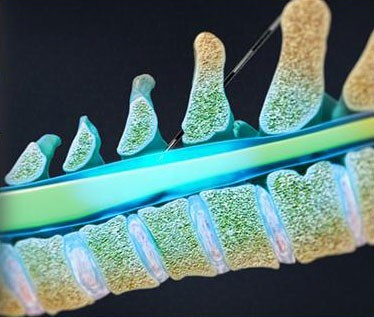

- Caudal Steroid Injection

- Facet Joint Injections

- Joint Steroid Injection

- Spinal Cord Stimulator Implant

- Discography

- Lumbar Epidural Steroid Injection

- Medial Branch Block